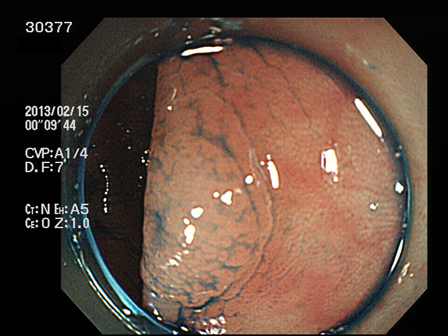

上記100名より抽出した平坦・陥凹型腺腫(=癌化の危険が高いが見落としやすい病変)の内視鏡写真

30366 30367 30372 30374 30375 30377 30379 30380 30381 30382 30383 30385